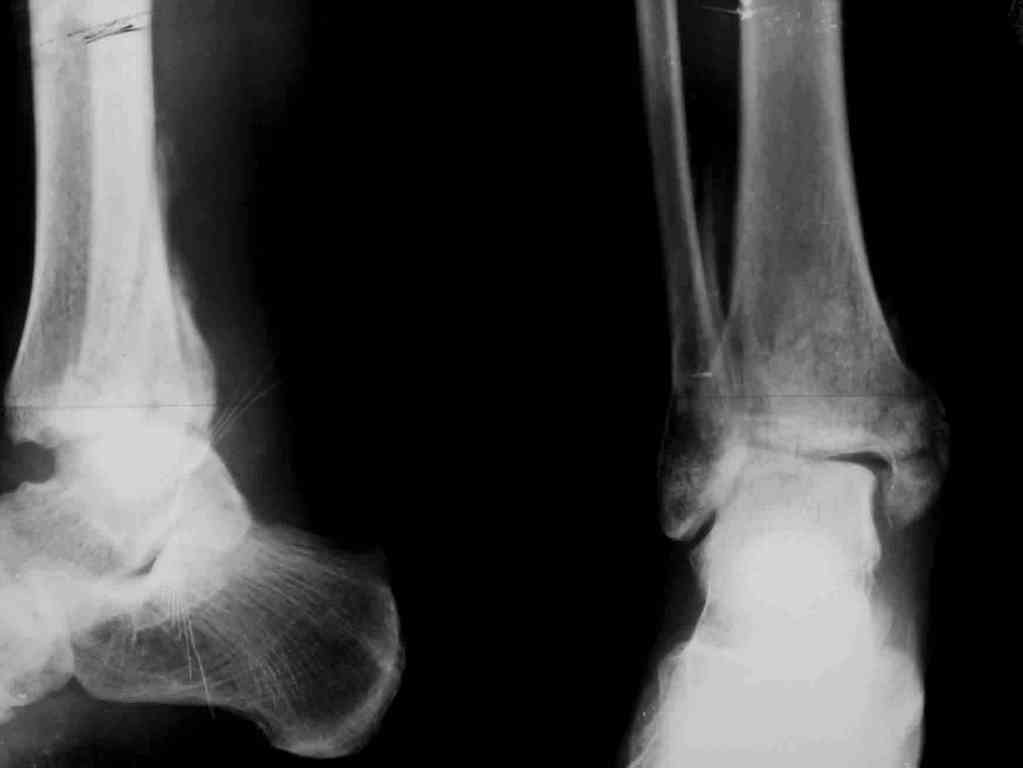

Два примера на снимках.Первый - врач 38 лет, неудачно оперированный в своей больнице с двухлодыжечным переломом, разрывом МБС был повторно оперирован через 8 месяцев. Пытались восстановить длину наружной лодыжки остеотомией, освежили МБС, два месяца функционального лечения без нагрузки на стопу.Сейчас ходит с легкой хромотой, устает к обеду, вальгусное отклонение стопы корригировано супинатором. На Рграммах видны дистрофические изменения латерального эпифиза большеберцовой кости.

Первый снимок через 6 месяцев после травмы, операции остеосинтеза болтом-стяжкой, удаленной по причине нестабильности и наличия свища над металлом.

Второй снимок через 3 месяца после реконструктивной операции.

Вторая пациентка 34 лет, перелом получала в Испании, где от операции отказалась, дома по приезду сняла скотчкаст и лечилась у костоправов, нагрузка с 3 недели. Операция через 3 мес после травмы. Остеотомия м-б кости, фиксация пластиной, восстановление МБС. Так как медиальная лодыжка подтянулась, суставная щель на ЭОП контроле нормализовалась ограничились латеральным доступом. Реконструкцию заднего края не пытались сделать тк там уже прослеживалась консолидация, а сминать эпиметафиз не хотелось. В настоящее время ходит с тростью \три месяца после операции\, сустав нестабилен-слабость дельтовидной связки. Супинатор и плотные кроссовки дают возможность длительно ходить.

Первый снимок сделан в Испании после репозиции, второй через 2 месяца после травмы перед операцией, третий-через 3 мес после операции.